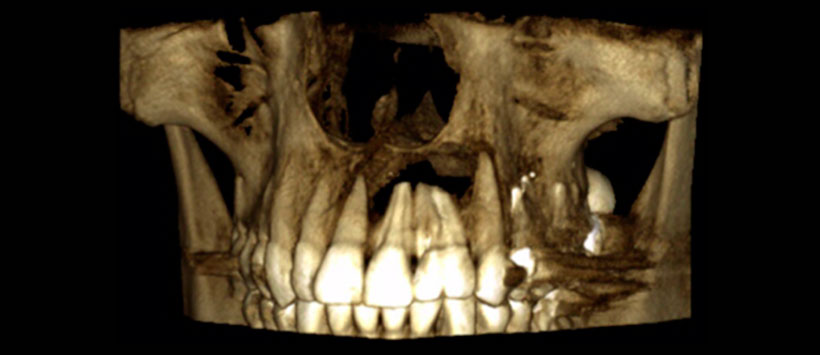

El paciente no presenta patologías de base, ni antecedentes de trauma bucal ni facial. Al examen físico se observa geminación de pieza 2.2, la cual presenta una restauración mesial (Figura 1) y aumento de volumen fluctuante levemente doloroso en el tercio anterior del paladar duro, con leve abombamiento de la tabla ósea vestibular.

A los tests de sensibilidad, solo es positivo para percu- sión, y es sensible a la palpación periapical. No hay cambios de color coronario, y los exámenes térmicos y eléctricos son negativos. Se solicitan radiografías convencionales, en las que se observa una imagen radiolúcida extensa de lími- tes netos no corticalizada, en relación a piezas 2.1, 2.2 y 2.3. Se complementa con tomografía computarizada Cone Beam (CBCT) (Figura 2), mostrando una imagen compatible con quiste radicular inflamatorio en pieza 2.2. Sus mediciones son 20 mm mesio-distal, 13 mm vestíbulo-palatino y 11 mm céfalo-cauda. Posterior al tratramiento, se le realizo una tomogriafia de control a los 20 meses para evalular el estado del tratamiento endoodntico asi como la cirugia.(Figura 3)